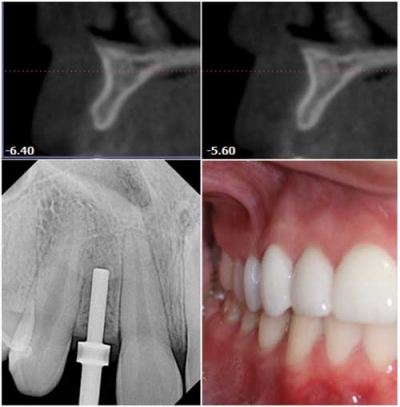

The ability to access the anatomical structures before starting the implant makes 3-D technology a good investment. The patient's chair time is greatly reduced with 3-D as a diagnostic tool. Without the CBCT scan, whether the patient needs one implant or a full arch of them, bone volume still has to be determined. With a CBCT scan, I will find out the dimension of the bone without taking a blade to the patient.

Patients appreciate that. Even with a 2-D panoramic, I would still have to anesthetize the patient and perform some bone sounding with calipers to find the buccal-lingual width of the bone. The scan illustrates precisely what is under the tissue, and the patient is put through less discomfort for a shorter time.

Today's implant techniques are more esthetically driven, and new technologies are mindful of this esthetic objective. I custom mill ceramic abutments and use IPS e.max® crowns using my E4D crown milling machine. This has been instrumental when preparing implants for the anterior region and designing the crown around the abutments.

Digital technology saves an astronomical amount of surgical time and improves the success of implants. When I can take digital (DEXIS®) PAs during surgery, I am sure that I am navigating between existing teeth and maintaining distance and parallelism. It is invaluable to me to have that information instantaneously. It shortens the time I have to wait with an open surgical site. Again, this is something patients appreciate.